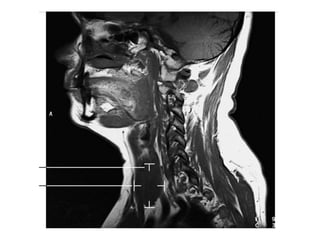

O documento fornece informações sobre como realizar exames de ressonância magnética do pescoço e angiorressonância magnética das carótidas, incluindo parâmetros, programação, anatomia, exames estruturais e funcionais, dicas e protocolos.